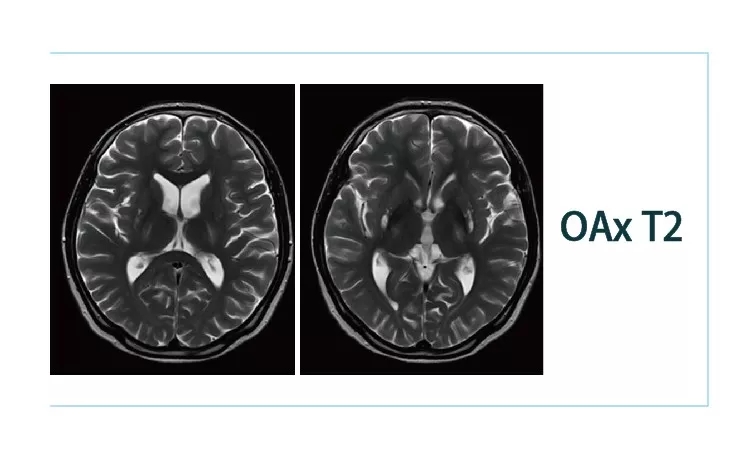

【朗润影像档案】20181130磁共振影像病例结果讨论